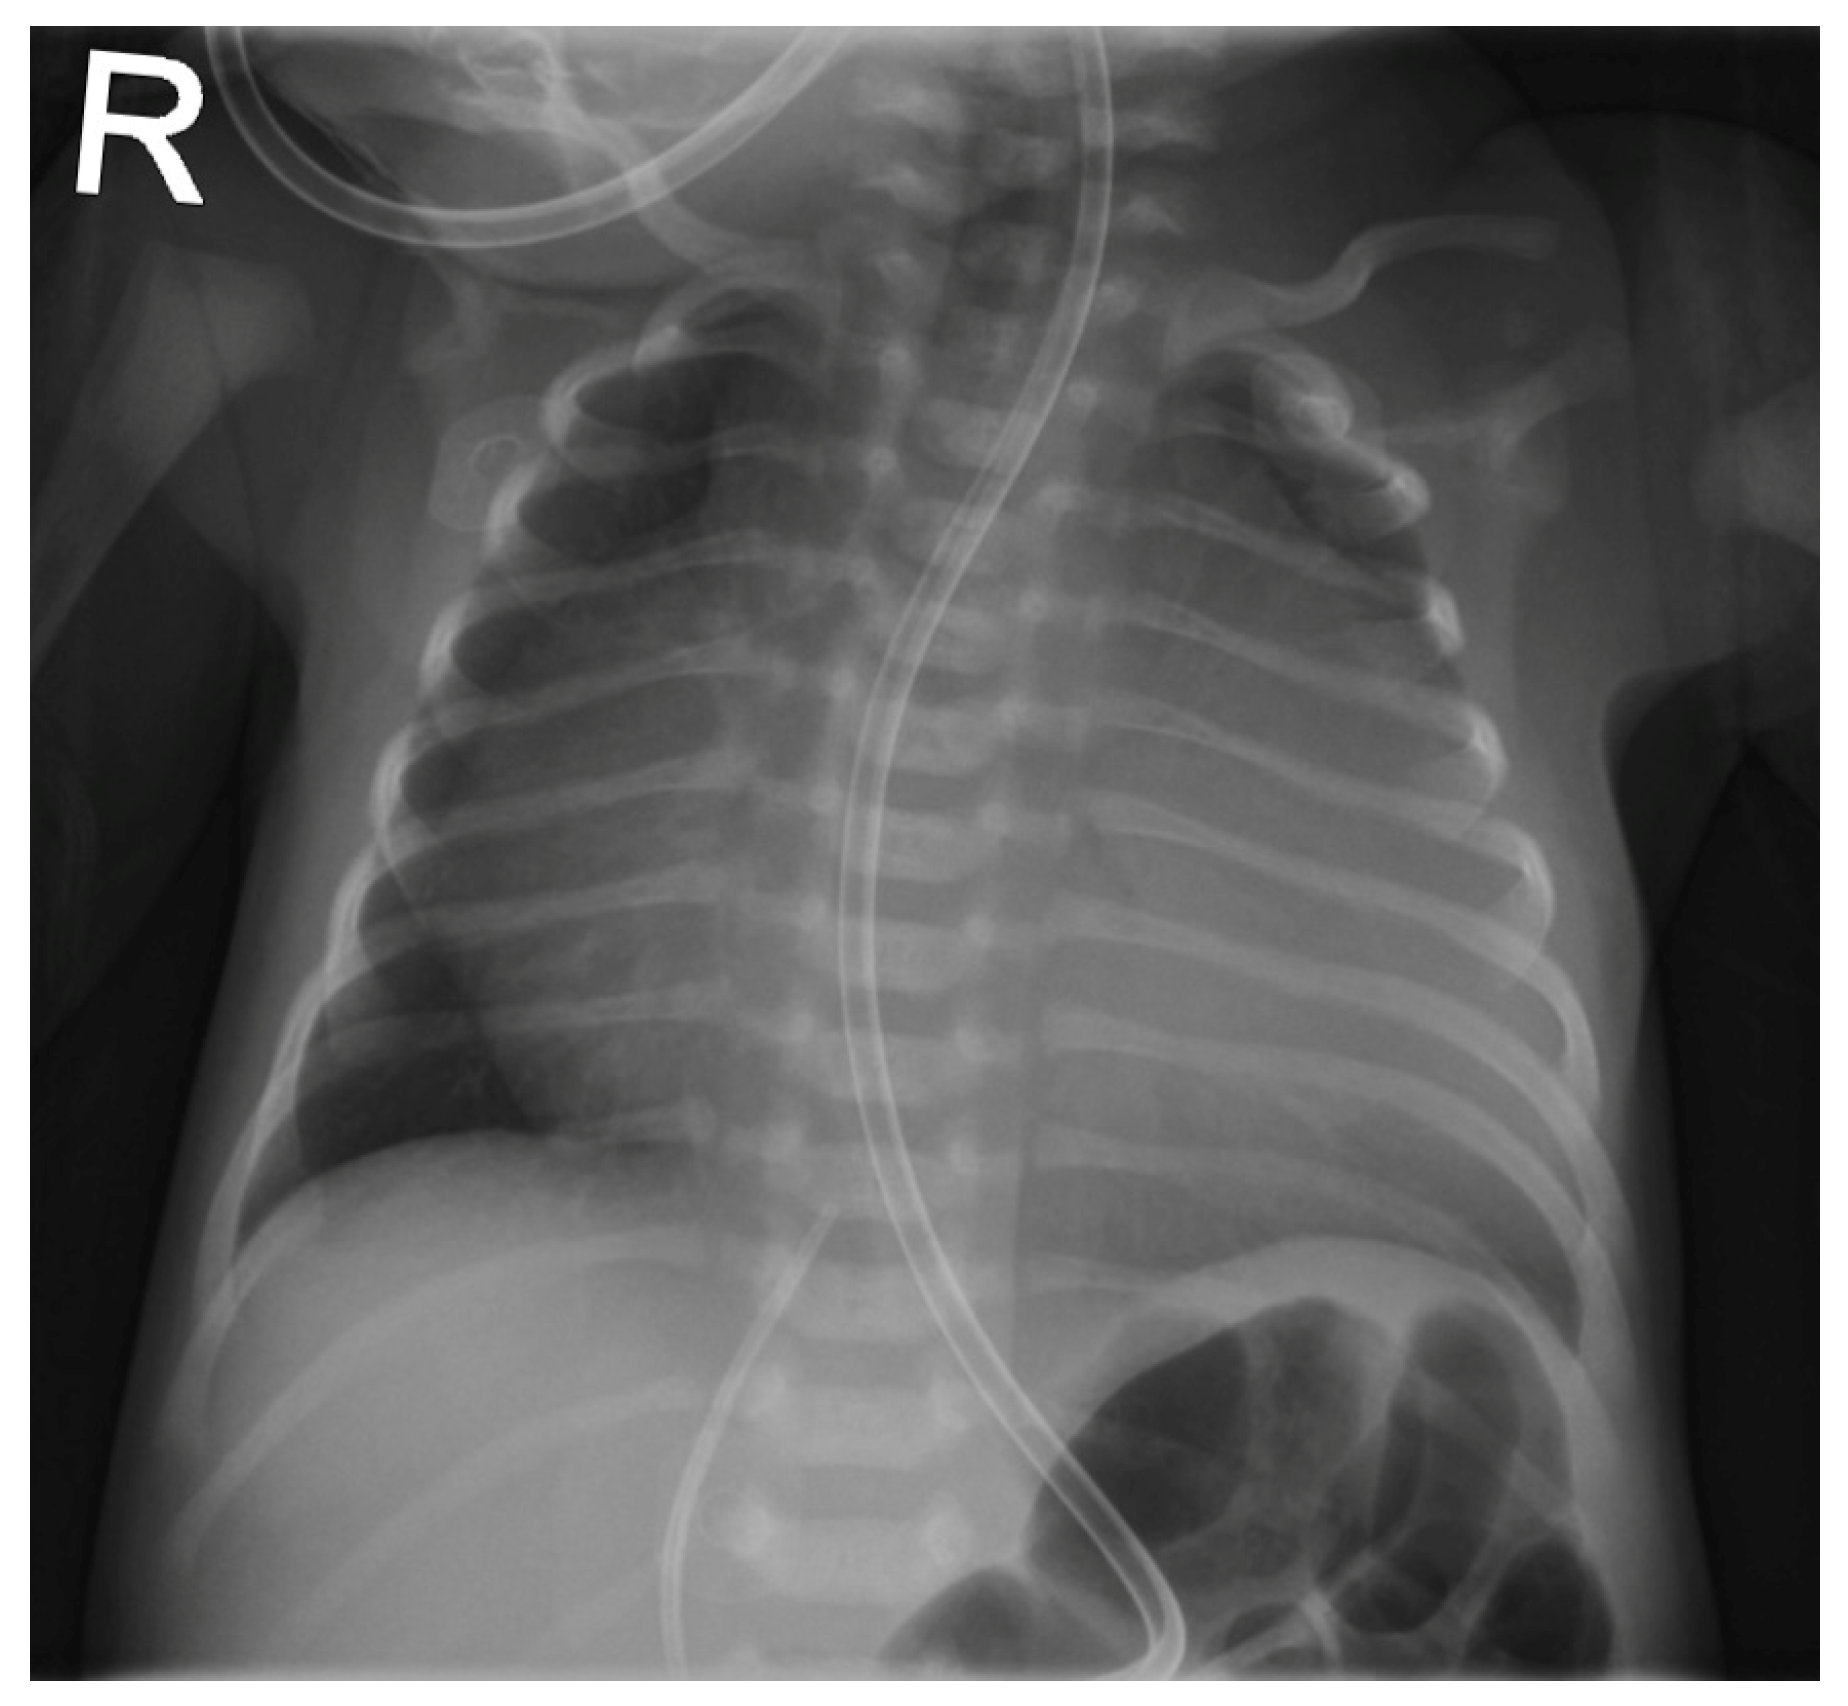

Entering the ninth month of the third year of life, CC revealed severe RPA branch stenosis (3.5 mm, z = −5.1), along with a dilated RV (EDV = 219 mL/m2) of severely impaired function (EF = 11%), requiring the implantation of a 6 × 12 Formula® stent (Cook Medical Inc., Bloomington, IN, USA). LPA measured 4.9 mm (z = −2.2) without branch or peripheral stenosis. The cardiac index was 4.6 l/min/m2 and CVP dropped from 18 to 5 mmHg after stent implantation. Within weeks after the procedure, RV function and dilatation improved significantly (see Figure 5 and Figure 6).

Figure 5. Cardiac catheterization, a.p.; (a) the stenting of the right pulmonary artery; (b) the left pulmonary artery for comparison; 18 months after cone reconstruction.